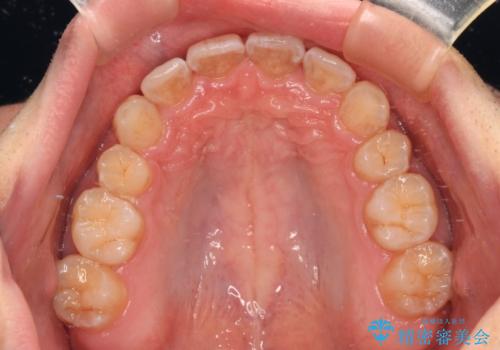

上下顎で左右差の大きい抜歯矯正を裏側装置で行ったため、非常に時間がかかりましたが、正中位置も良い位置に改善され、気になっていた突出感も解消されました。

出っ歯と八重歯 目立たない裏側装置でスッキリとした口元に